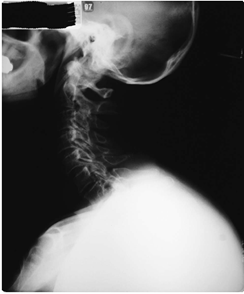

上の写真は正常な頸椎の前弯を示しています。

頸椎は、前弯(Cの字のように前に弯曲している)しているのが通常の形となります。

脊椎のコブ角は最も傾いている2つの椎体のなす角度から求めますが、7つの頸椎のうち2番目の椎体(C2)上縁と7番目(C7)の椎体下縁の間で線を引いてα(コブ角)を計測したとの記載がありました。また、本文献においては、正常な頸椎のコブ角は21~43度の範囲内とされています。